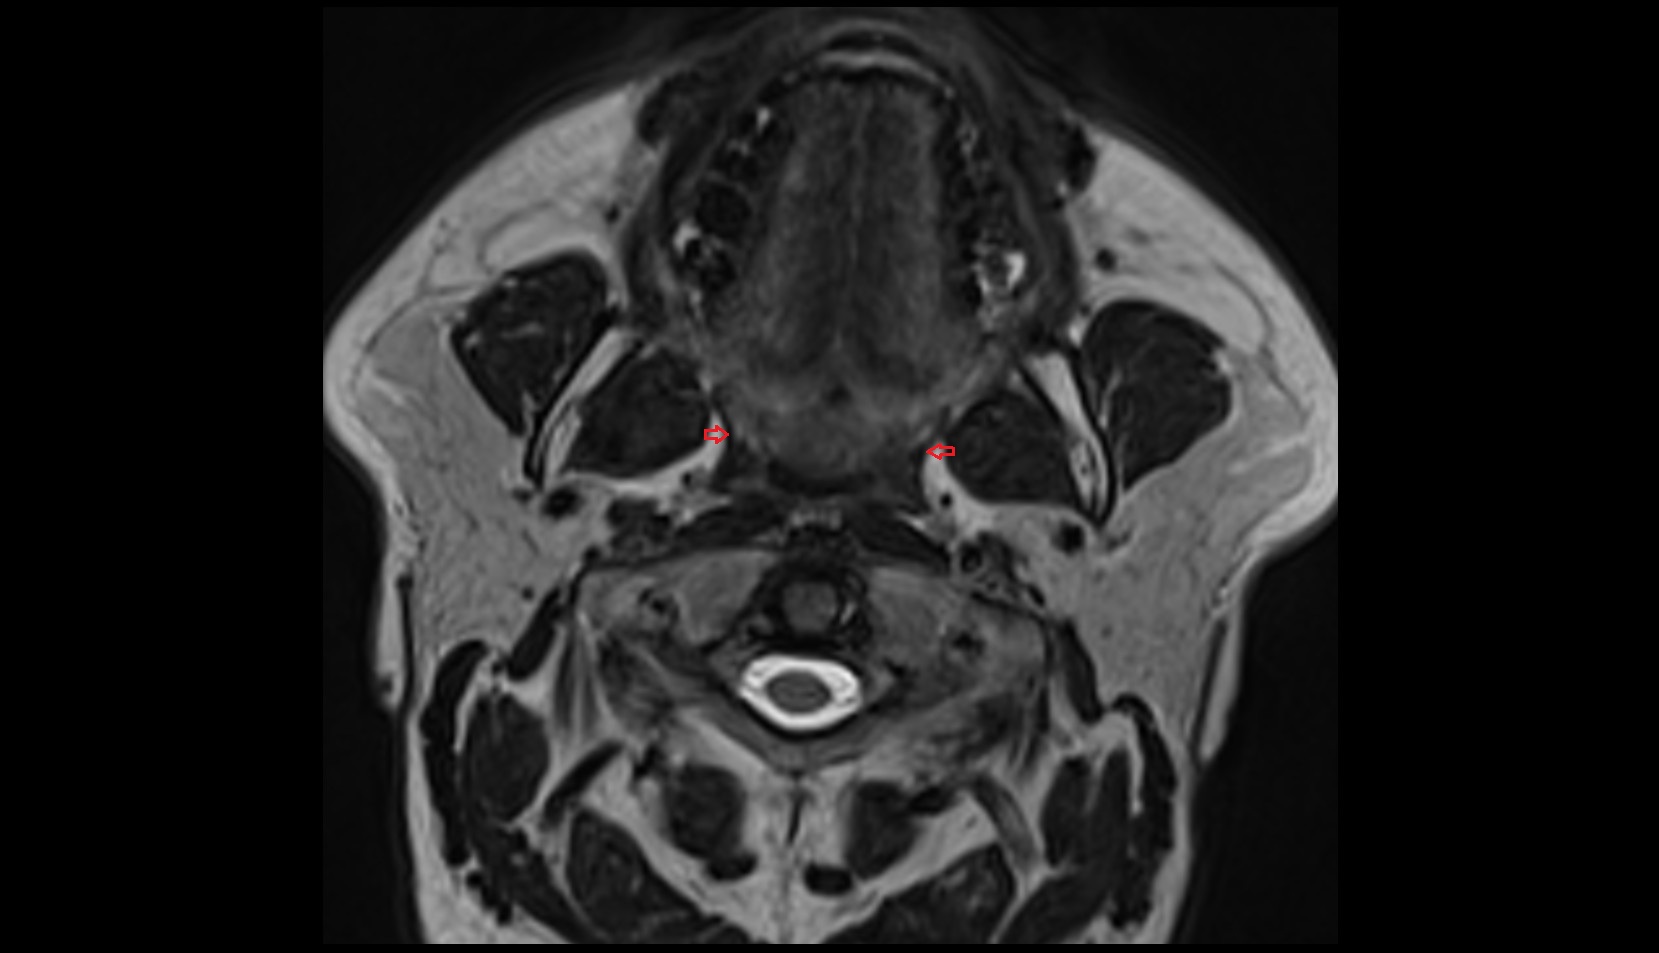

- Temporomandibular joint

- Mandibular condyle

- Mandibular fossa